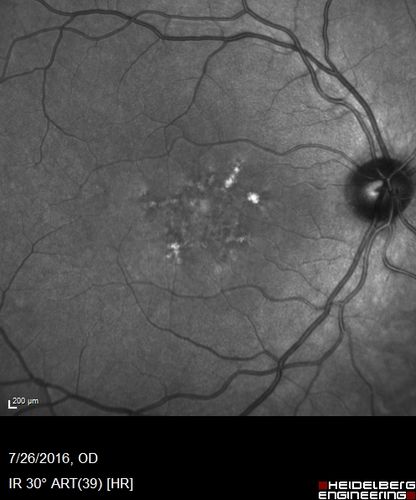

Pattern Dystrophy - Probably Early Butterfly

33 year old with normal vision and no visual complaints - normal color vision